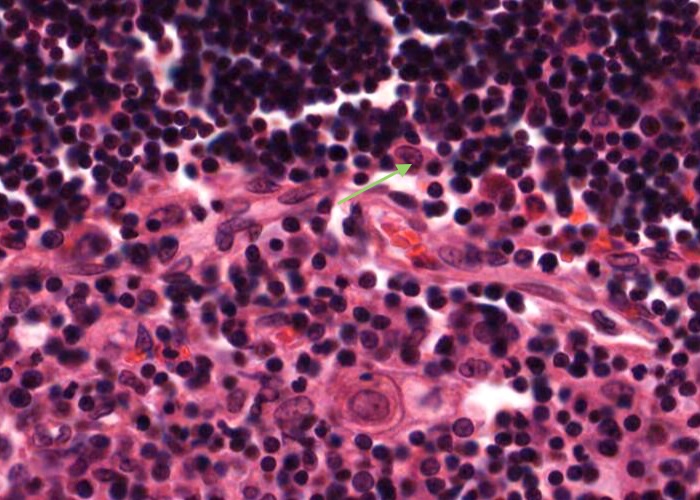

A type III epithelioreticular cell can be seen at the boundary of the cortex and the medulla. They are similar to type 1 cells in functioning as a barrier that isolates developing T- cells between the cortex and medulla.

There are also a substantial number of macrophages in the cortex but you will not be able to distinguish them from epithelial reticular cells in this H&E preparation. If a large pale nucleus has a substantial amount of cytoplasm around it it probably belongs to a macrophage instead of an epithelial reticular cell.